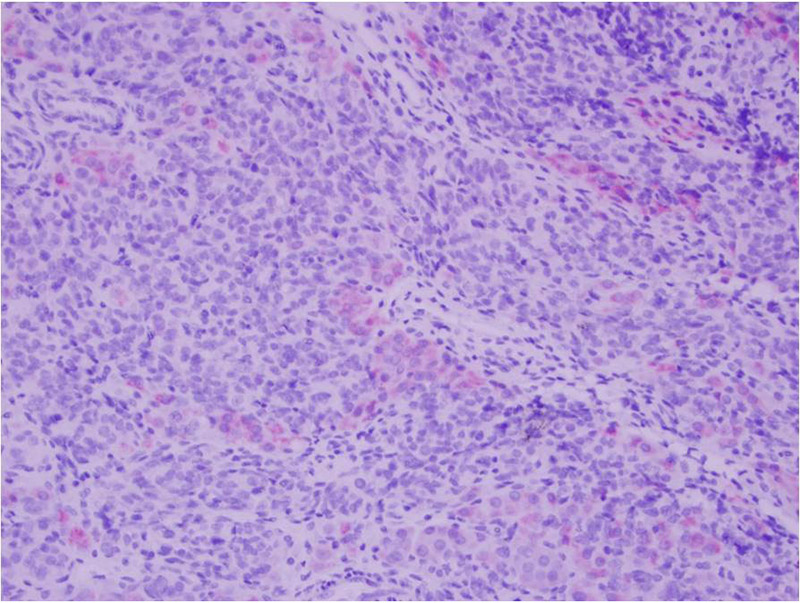

On microscopic examination, the specimen showed a lobulated hypercellular tumor consisting of 2 cell populations. The predominant population was columnar basophilic cells arranged in irregular cords and nests with vague tubule formation. There were also small infrequent nests and clusters of plump eosinophilic to pale cells with round nuclei containing prominent nucleoli (Figures 1 and 2).

Scattered throughout the specimen were areas with heterologous sarcomatous elements, showing a spindle cell population with marked pleomorphism and hyperchromasia (Figures 3 and 4).